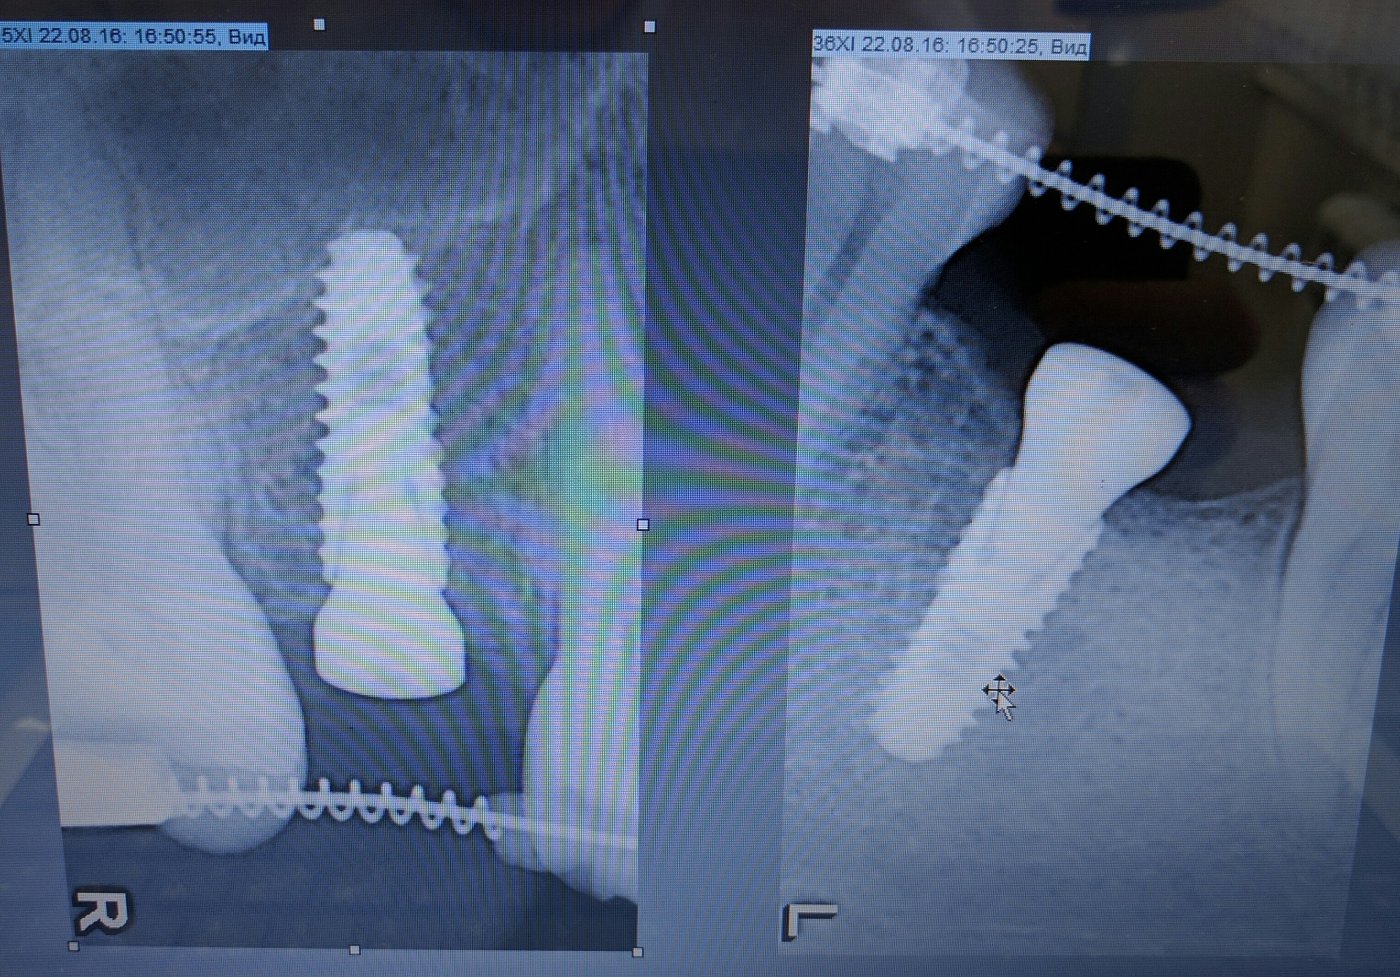

Имплантацией занимаюсь с 2013 года, преимущественно с корейскими системами имплантатов Dentium, Osstem.

Так же есть опыт в установке израйльских имплантатов Noris, Mis, Alpha Bio, и швейцарских имплантатов SIC.

Из навыков: открытый и закрытый синус лифтинг, одномоментная имплантация , расщепление альвеолярного гребня, sausage technique и другая направленная костная регенирация, опыт в работе с титановыми сетками на имплантатах Osstem система Smart Builder, мягкотканная пластика десны, пародонтологические операции. Удаление зубов любой сложности, чтение клкт (3D) и составления рационального плана лечения, стремление расти и развиваться профессионально!